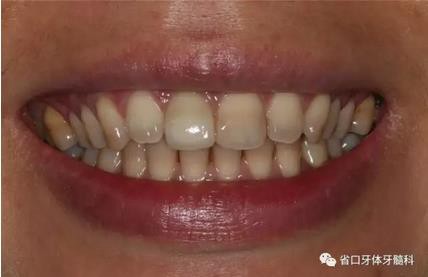

圖1 術(shù)前口內(nèi)照

圖2 術(shù)前口內(nèi)照

圖3 術(shù)前口內(nèi)照

上頜右側(cè)中切牙修復(fù)體固位良好,牙齦乳頭充盈良好,齦緣水平對(duì)稱 修復(fù)體與對(duì)側(cè)同名牙協(xié)調(diào)一致。外觀笑容美觀協(xié)調(diào)?;颊邼M意。X線檢查示 上頜右側(cè)中切牙種植體周穩(wěn)定骨質(zhì)包繞,唇側(cè)骨板>2mm,相鄰牙槽骨高度穩(wěn)定,基臺(tái)及修復(fù)體就位良好。分別根據(jù)Furhauser的PES和Bulser的WES 進(jìn)行美學(xué)評(píng)分,總分值為20,美學(xué)效果良好。